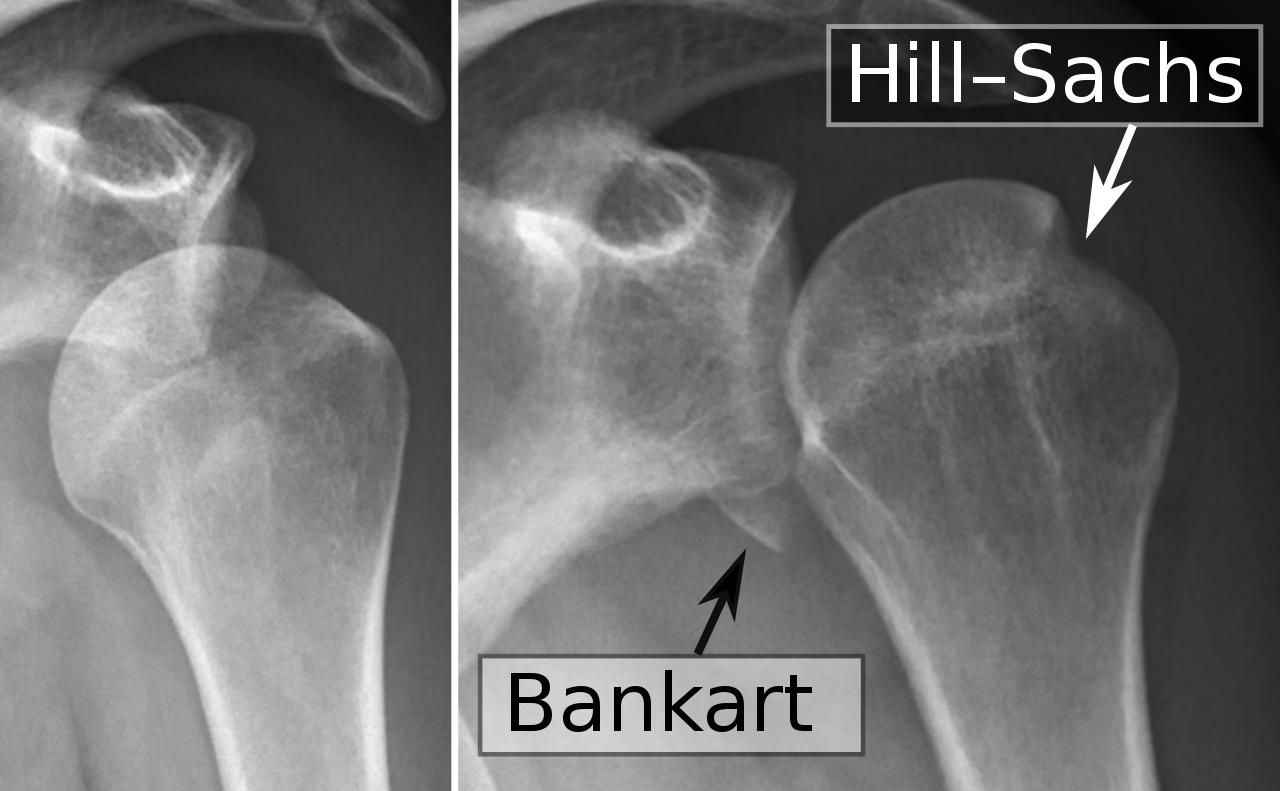

What is a Bankart lesion?

What is a bony Bankart lesion?

What is a Hill Sach’s lesion?

Impaction injury to the chondral surface of the posterior and superior portions of humeral head (present in 80% traumatic dislocations)